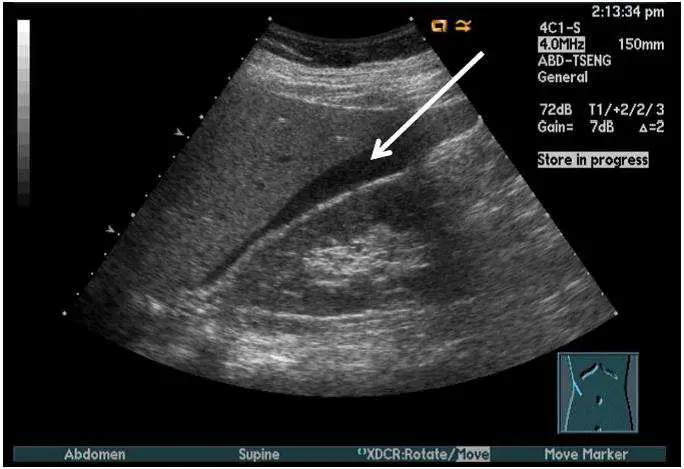

如附圖為腹部超音波影像,箭號所指為下列何者?

本張腹部超音波影像可見:

- 中央有一大型、邊界清楚的無回音(黑色)圓形結構,為充盈的膀胱(urinary bladder)

- 兩個黃色箭號指向膀胱後下方一層新月形/薄層無回音液體

- 此液體層沿著膀胱外側壁分布,呈薄層、可移動的特性

- 液體呈純無回音,邊緣清晰,無內部回音或分隔

- 此位置(膀胱後方)為腹水在骨盆腔的典型蓄積部位(Douglas 氏腔/直腸膀胱陷凹)

兩個箭號所指的薄層無回音積液為**腹水(ascites)**的典型影像表現。

(A) 腹水 ✅ — 正確。超音波顯示膀胱旁/後方有薄層無回音積液,符合腹水在骨盆腔蓄積的典型表現。自由流動的腹水為均質無回音,呈現月牙形或沿臟器分布的特徵。